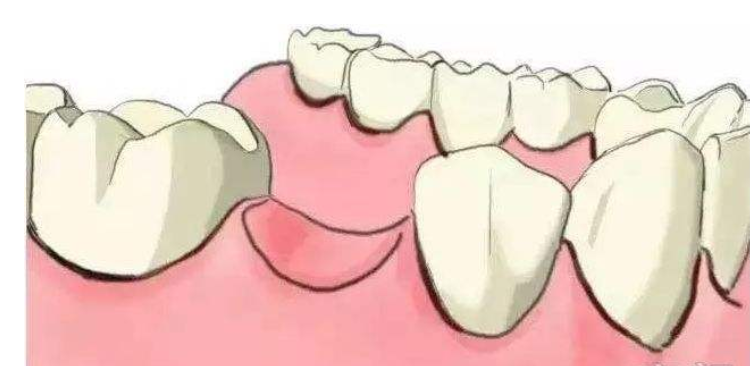

三、缺失三颗,无论前牙区还是后牙区,多数是种植两颗,而且多数时候是种在两边,中间用架桥的方式修复,偶尔也会选择种植三颗,种植两颗还是三颗主要考虑种植体不能距离过近,同时也考虑治疗的费用。

四、缺失四颗,在前牙区,一般考虑种植两颗架桥,后牙区结合患者年龄、对颌牙状况、饮食习惯等等选择种植两颗或三颗,假如是年轻人,对颌牙非常健康,又喜欢咀嚼硬物,种植三颗是比较合适的设计,年纪大了,不再喜欢吃过硬的食物,可以考虑种植两颗架桥的方式。